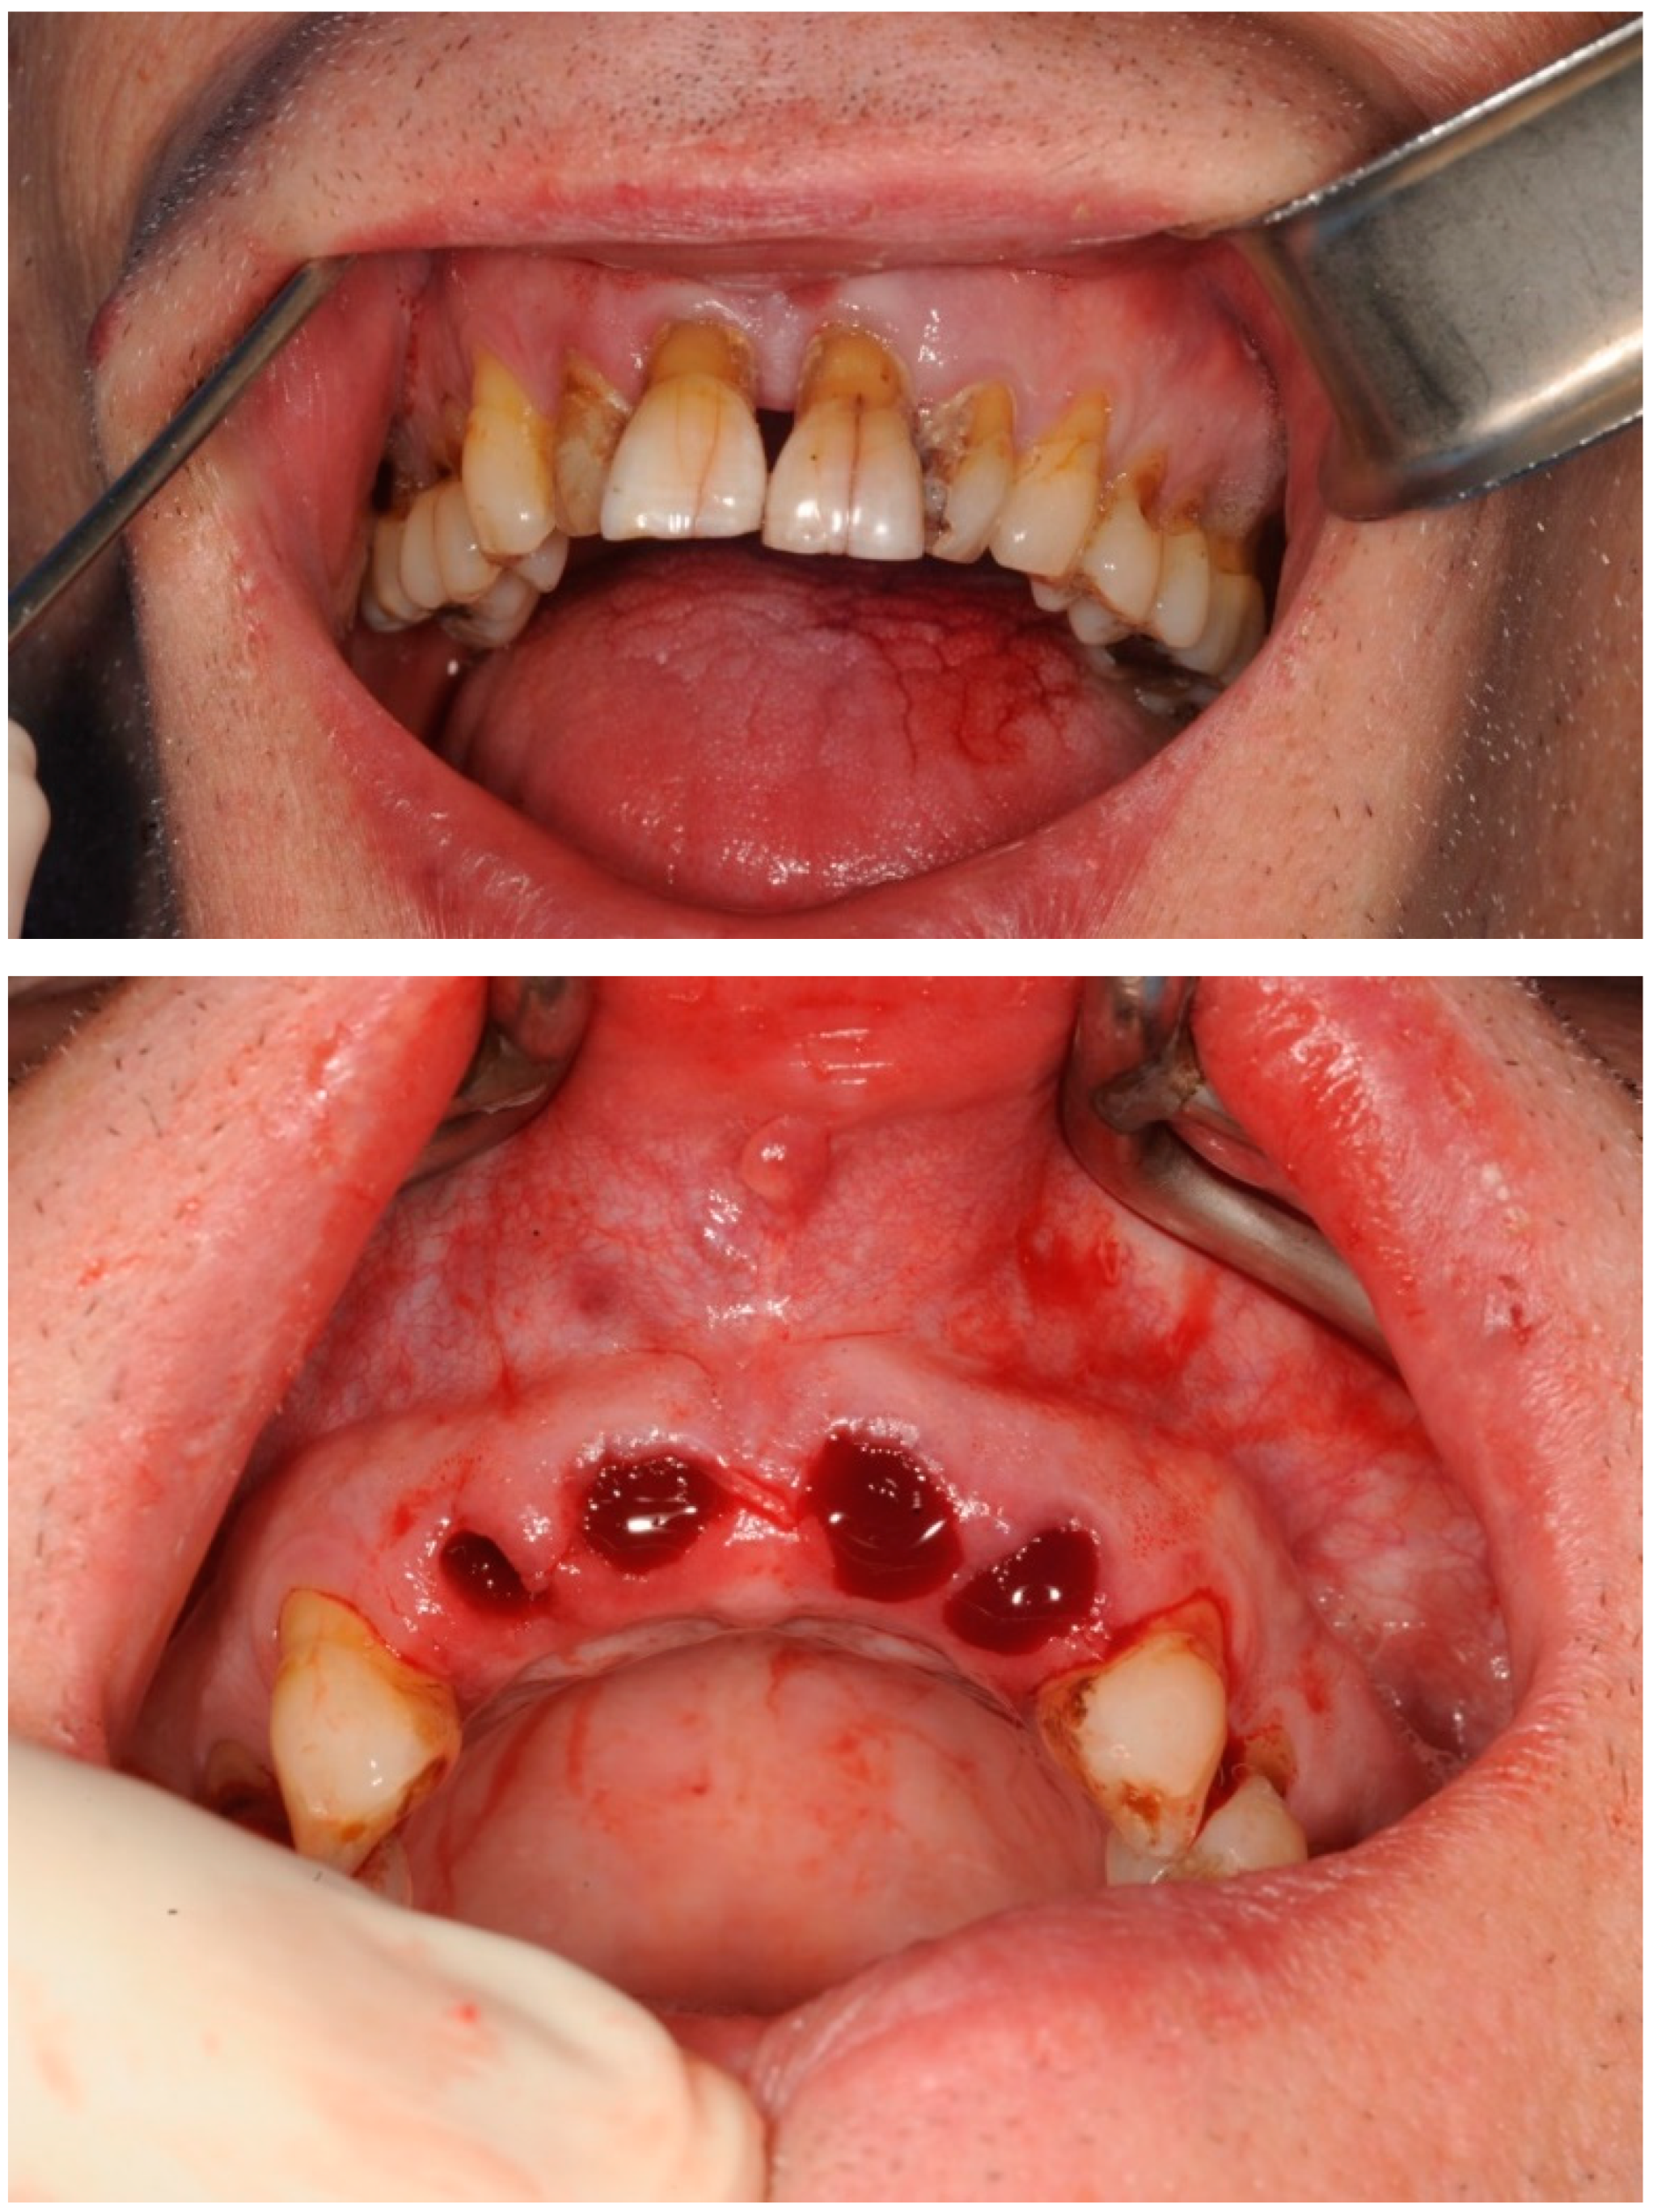

3.2. Case Study 2